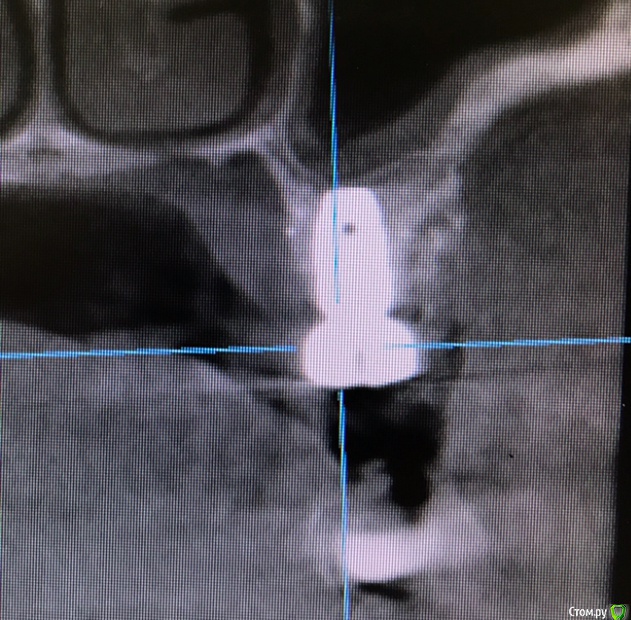

колесников Опубликовано 15 марта, 2019 Автор Поделиться Опубликовано 15 марта, 2019 Вот так выглядит интегрированый графт и соответственно не созревший. Время ожидания примерно равнозначное Ссылка на комментарий

колесников Опубликовано 16 марта, 2019 Автор Поделиться Опубликовано 16 марта, 2019 (изменено) Ну как бы тут все очевидно. Слева стала костью,справа нет. Но должен вам отметить,что даже в случае неудачи (как кажется)потери нет. Задача стояла не увеличить объём для имплантации или укрыть Имплант,а снять напряжение с вершины гребня и дать созреть десне. Имплант в нативной кости,он интегрирован,десна успела созреть за это время,возможно будет не так объёмно как хотелось бы,но у меня в запасе этап раскрытия ,фдм зарос ,есть с чем поработать. Все что не интегрировалось ,лизируется самостоятельно,выскребать ничего не нужно,ещё подождать. Изменено 16 марта, 2019 пользователем колесников Ссылка на комментарий